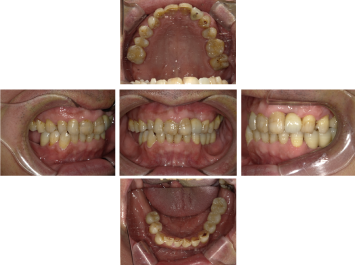

30代 女性 奥歯 インプラント

| 年代・性別 | 30代・女性 |

| 治療回数 | 10回(術前治療・検査除く) |

| 治療期間 | 約1年 |

| 料金 | ¥410,300(税込)※別途検査料 |

| 特徴 |

失った歯を補うために、インプラント治療は優れた治療方法です。 しかし、全ての人にインプラント治療が優れている治療ではありません。 |

| 副作用 | 術後に腫れ・痛みが出る可能性がある。 |